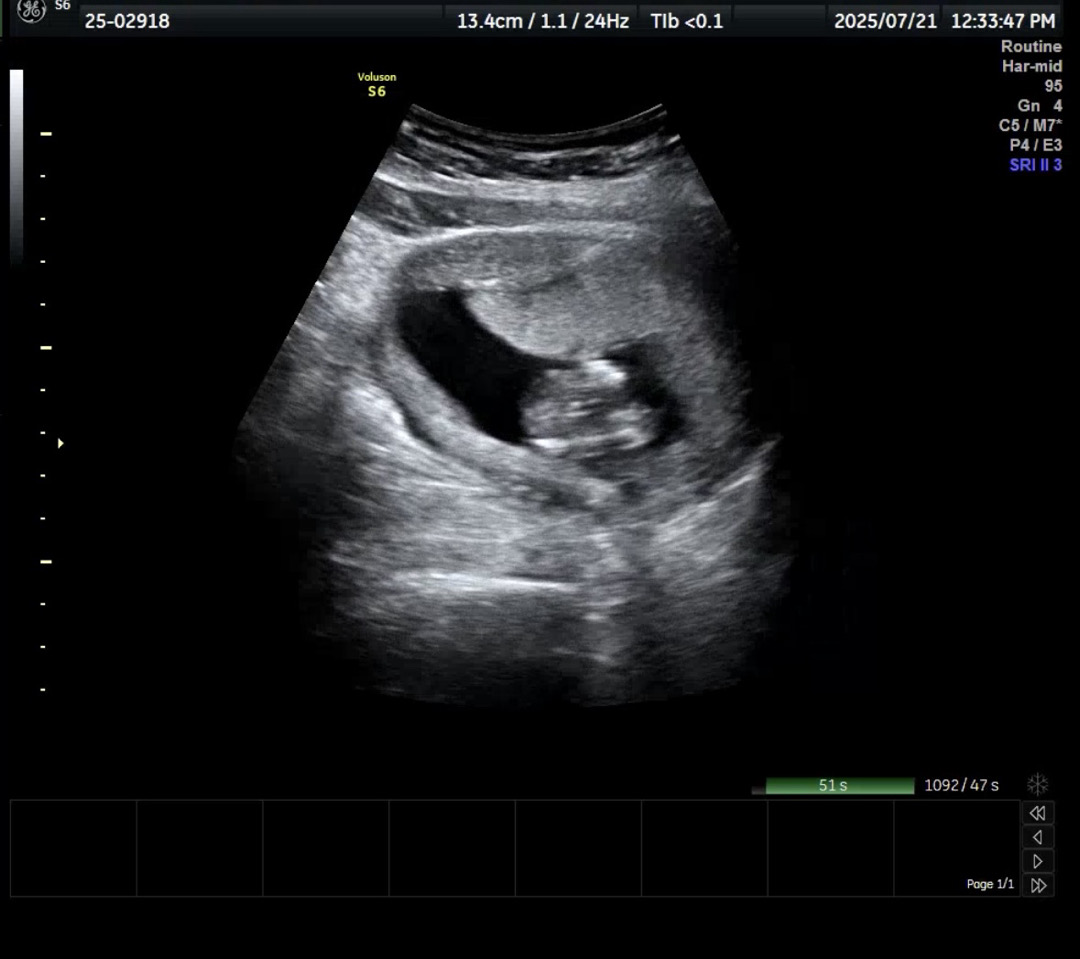

14주차 각도법 성별 좀 봐주세요!

첫 아기고 저희 부부는 너~무 딸을 원해요.

저희딸도 저렇게 밑에서 보니 소중이가 마카롱(?) 모양이더라구요 ㅋㅋㅋ 딸 아닐까요??

각도법 볼 수 있는 사진이 아닌 것 같아요~ 옆모습 없나요?